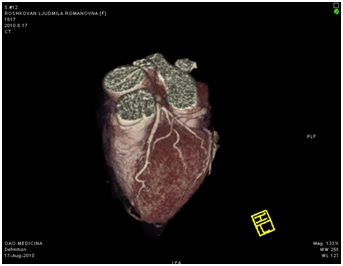

МСКТ коронарных артерий от 08.2010

Ствол ЛКА широкий, имеет ровные контуры, не стенозирован. ПНА в проксимальном сегмента имеет неровные контуры за счет кальцинированных и частично кальцинированных бляшек, просвет артерии на этом уровне сужен до 30-50%, в среднем сегменте определяется ряд пристеночных и циркулярных мягких бляшек, со стенозом артерии до 60-75%, дистальные отделы артерии малого калибра, плохо заполняются контрастным веществом. ОА нормального диаметра, заполняется контрастным веществом без признаков гемодинамически значимого стеноза. ПКА нормального диаметра, в проксимальном сегменте имеются смешанные частично кальцинированные бляшки, стенозирующие просвет до 30%, в среднем сегменте визуализируется пристеночная смешанная бляшка, стенозирующая просвет до 50-70%, дистальный сегмент не изменен. Правый тип коронарного кровоснабжения.

Трехмерная реконструкция